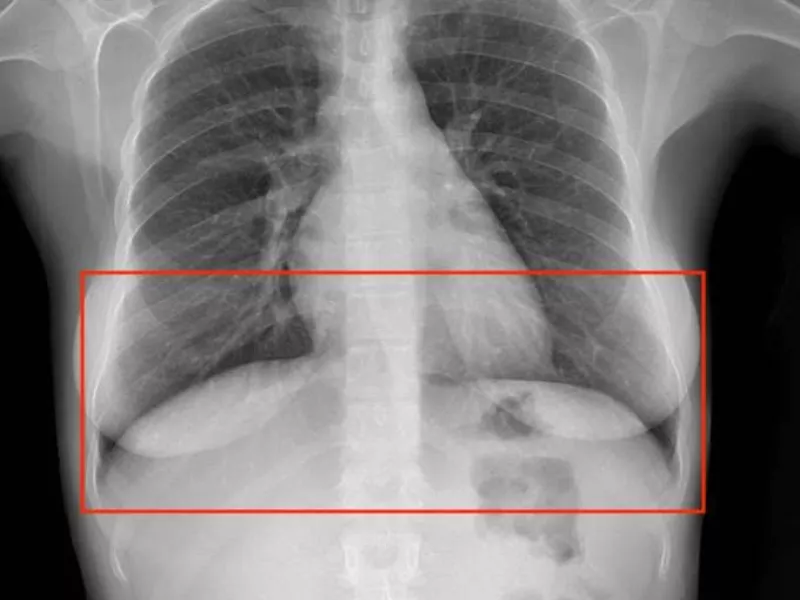

Bounding Box

This type draws rectangular regions around objects of interest within images. As the simplest technique, it is ideal for object detection tasks. Experts often use it to label images, such as identifying simple fractures or foreign bodies in a standard X-ray or digital imaging files.